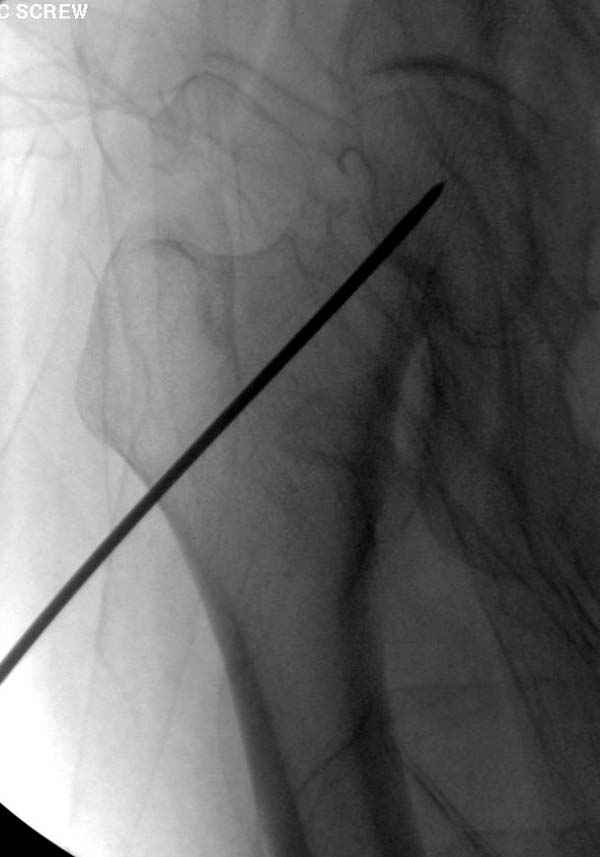

Профилактику дальнейшего раскола неполного перелома шейки провели тремя канюлированными шурупами.

Наверное речь идет насчет parallel guide из набора. Применяем по возможности всегда, но,

как видно на снимке, не всегда получается

паралельно.

Такие несмещенные переломы обычно для молодых резидентов, и бывают технические неточности, но в этом случае посчитали фиксацию адекватной.

Соблюдая правила, многократными попытками можно

увеличить риск стрессового перелома латерального

кортекса.